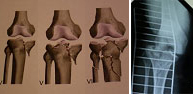

La articulación de la rodilla compromete los extremos inferior del fémur y superior de la tibia. Además se encuentran implicadas las estructuras ligamento-meniscales de esta región lo que hace de su tratamientouno de los más complejos del esqueleto. Las lesiones óseas a este nivel son producidas por traumatismos de alta energía, desde accidentes de tráfico y caídas desde gran altura hasta deportes como fútbol, rugby, artes marciales, deportes de motor, esquí, etc. El enorme abanico de lesiones a este nivel requiere de un estudio detallado antes de tomar decisiones de tratamiento. Los últimos avances en técnica artroscópica han permitido la realización del tratamiento a través de heridas de mínimo tamaño por las que se introduce una cámara óptica permitiendo la reparación de la lesión bajo visión directa en una pantalla.